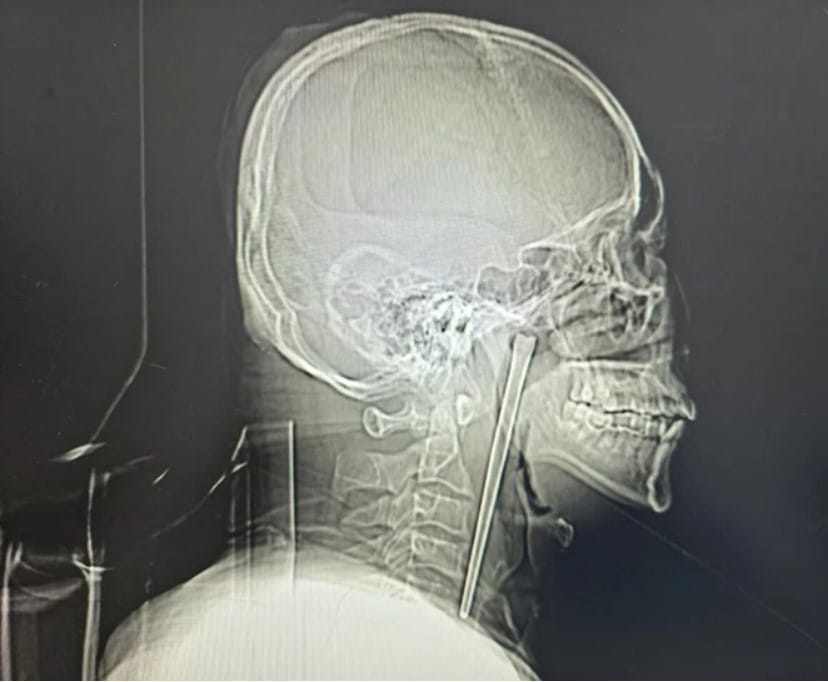

Yapılan incelemelerde adamın boğazında tam 12 santimetre uzunluğunda metal bir yemek çubuğu olduğu saptandı. İşin en sarsıcı yanı ise bu yabancı cismin tam 8 yıldır orada olduğunun ortaya çıkmasıydı.

12 santimetrelik paslanmaz çelik çubuk dokulara daha fazla zarar vermeden büyük bir titizlikle vücuttan tahliye edildi.